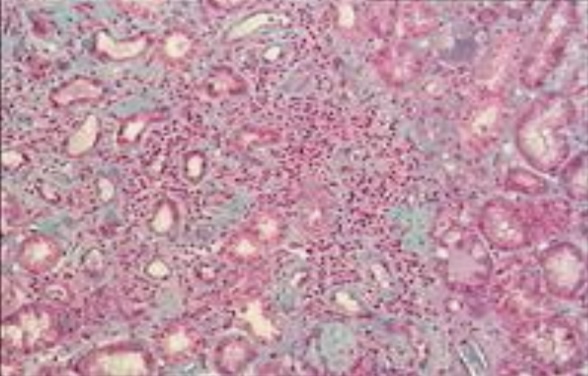

Silicosis